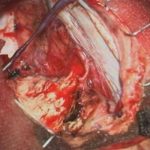

下垂体腺腫

頭蓋内腫瘍摘出術

No.’25_34 摘出 後